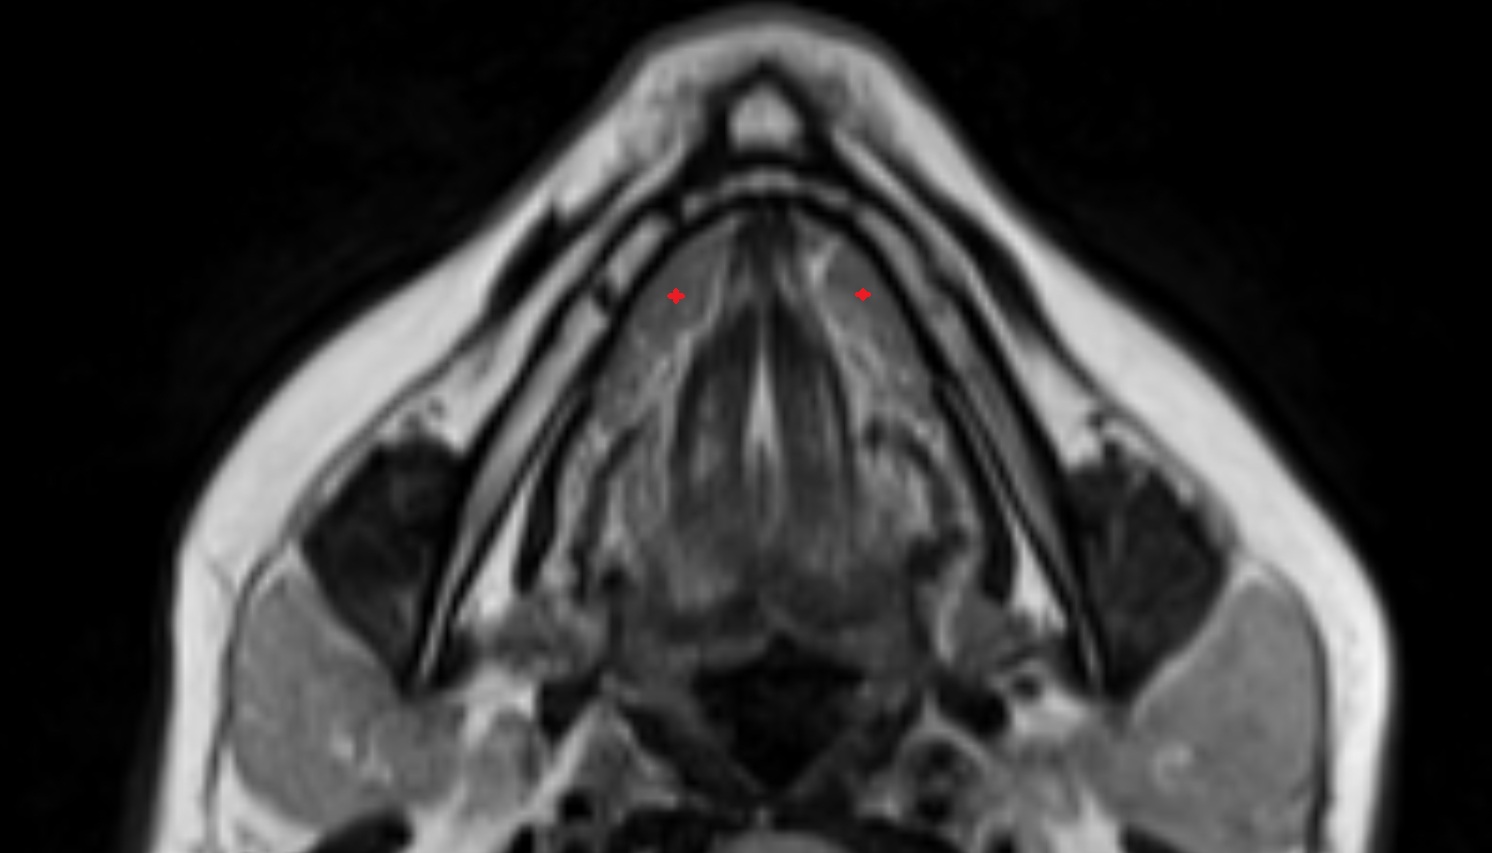

- Submandibular gland